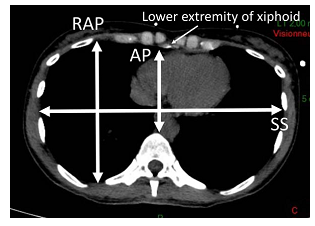

该团队创新性提出GW/RAP(移植物重量与受体右侧前后径比值)联合GRWR(移植物与受体体重比)作为LFSS的预测公式,其优势在于:①GW/RAP考虑到受体右上腹前后径与移植物的个体化差异(见下图);②GRWR除了具有预测LFSS的作用,还是临床上用于预测小肝综合征(SFSS)的最重要指标,从而在术前杜绝供肝裁剪过度的风险;③以上两个参数测量简便,不依赖于供体的影像学检查,保证了供体在器官维护过程中的安全性。

RAP测量